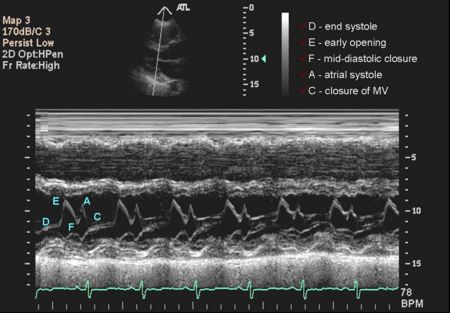

Mitral Valve M-mode Analysis

- Anterior leaflet with E/A appearance of diastology

- Decreased EF slope in MS

- Scalloping of leaflet tip in end systole in prolapse